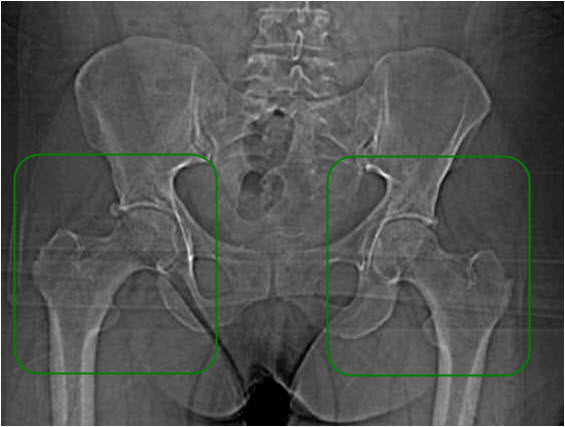

Dysplazja i zwichnięcie stawu biodrowego u dorosłych

Staw biodrowy to największy staw kulisty panewkowy u człowieka. Jest on stabilizowany za pomocą więzadeł, ścięgien i torebki stawowej. Staw biodrowy tworzy wypukła główka kości udowej oraz wklęsła panewka miednicy, które pokryte są gładką powierzchnią stawową. Dzięki temu, ruch w stawie odbywa się w sposób płynny i bezbolesny. Obrąbek panewkowy odpowiada za utrzymanie mazi stawowej oraz jest naturalną granicą stawu biodrowego.

Dysplazja stawu biodrowego oznacza, że panewka ma nieodpowiedni kształt, przez co nie jest w stanie prawidłowo „objąć“ główki kości udowej. Powoduje to dużą niestabilność i bolesność stawu, a także asymetrię ruchów.

Pierwszym objawem dysplazji bioder u osób dorosłych jest właśnie bolesność stawu (szczególnie podczas wzmożonych aktywności), a także utykanie. Rzadziej obserwujemy charakterystyczny dźwięk „przeskakiwania” w trakcie ruchu.

W medycynie wyróżniamy 6 typów dysplazji stawów biodrowych, które rozróżniamy w zależności od zaawansowania procesu chorobowego oraz czasu jego powstania1:

- Dysplazja bioder

- Rozwojowe zwichnięcie stawu biodrowego (DDH)

- Zwichnięcie biodra

- Rozwojowa dysplazja stawu biodrowego (DDH)

- Dysplazja panewki stawu biodrowego

- Wrodzone zwichnięcie stawu biodrowego (CDH)

u 29-letniej kobiety.

Nieleczone zwichnięcie bądź dysplazja stawu biodrowego prowadzą do zaawansowanych zmian zwyrodnieniowych, a w rezultacie nawet do kalectwa!